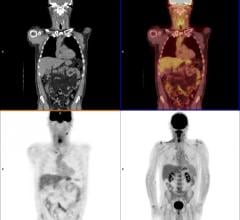

Cancer is perhaps the most highly personal, complex disease in our world today. While the various types of cancer are ...

September 7, 2017 — Advanced melanoma has a poor prognosis, but immune checkpoint inhibitor therapy can be effective for ...